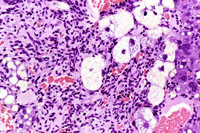

This hemangiosarcoma is has caused degenerative changes in some of the entrapped hepatocytes. The degenerating hepatocytes are enlarged and vacuolated with evidence of nuclear degeneration.